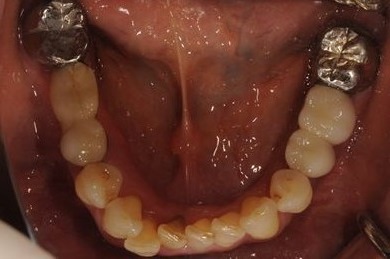

インプラントの症例写真 IMPLANT

骨再生インプラント治療

| 性別/年齢 | 女性 / 51歳 | ||||||||||||||||||||||||||||||||

| 主訴 | 他の歯科医院で入れ歯を入れたが、滑舌や味などで不自由を感じている。インプラントは難しいと言われたが、可能かどうかみていただきたい。 | ||||||||||||||||||||||||||||||||

| 治療内容 | インプラント3本(サイナスリフト)、ハイブリッドセラミッククラウン5本 | ||||||||||||||||||||||||||||||||